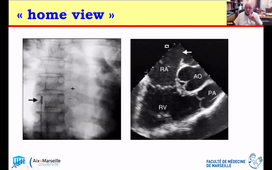

Echo de stress 1 - Valvulopathies - Pr HABIB

CIA et FOP - diagnostic et guidage fermeture - Pr HABIB

ETO - indications et valvulopathies - Dr DERNYS

ETO et pathologie aortique - Dr ARREGLE